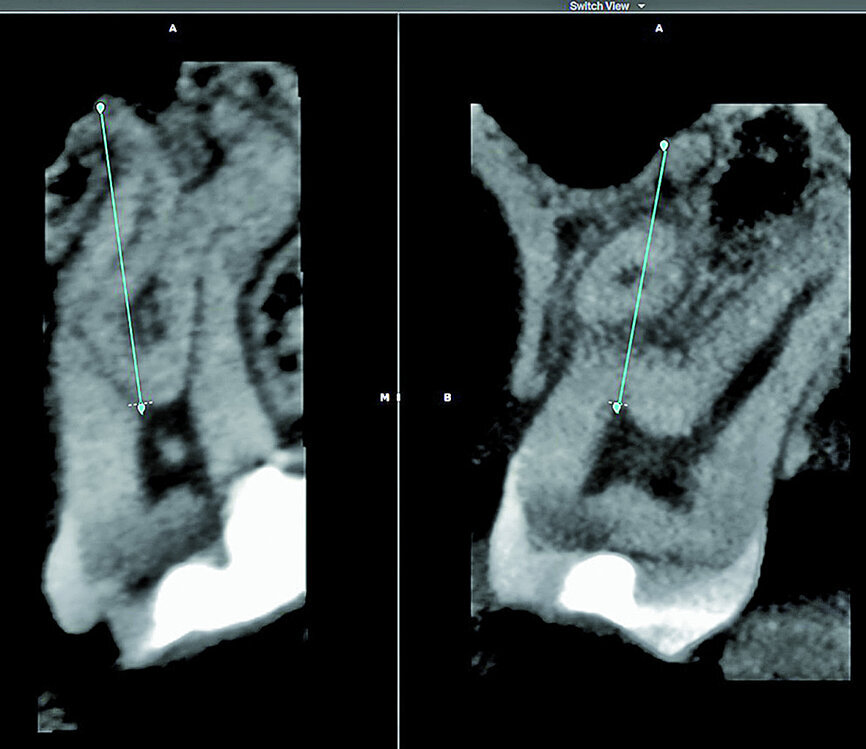

With the fourth step, ‘3D Canal Anatomy’, the software made a proposal of the canal anatomy (Fig. 7), but the operator can make corrections according to the canal configuration that can be viewed in different planes in the software. Figures 8 to 10 show the mapping of the palatal, mesiobuccal, and distobuccal root canal systems.

During the fifth step, ‘Treatment Plan’, the software projected ISO size 06 instruments into the canals (Fig. 11), which allowed the operator to visualise the internal anatomy of the canals, check straight line access, and modify the proposed access if necessary. A rubber stop on the files can then be digitally adjusted to a coronal reference point of choice that will then indicate the proposed working length for each root canal system. This view can also be rotated in 3-D to alert the operator of the angle and direction of curvatures in the root canal systems (Fig. 12). The step after ‘treatment plan’ is to select a master file from a preloaded database of endodontic file systems that will most likely result in optimal canal preparation for that specific shape or diameter of a canal. Considering the s-shaped curvatures in all three root canal systems as well as the sharp curvatures in different planes, it was decided to use the Primary WaveOne Gold file (25/07) in the palatal canal and the Small WaveOne Gold file (20/07) for root canal preparation in the two-challenging buccal root canal systems (Fig. 13). The selected instruments were then displayed in the root canal systems and the operator again digitally rotated and visualised the root canal anatomy in 3-D (Fig. 14).